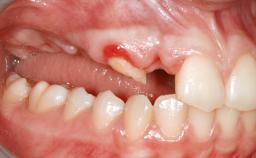

A 47-year-old woman who had suffered from aggressive periodontitis requiring a number of periodontal interventions over more than 10 years was referred by her general dental practitioner and periodontologist for bone augmentation and implant therapy. Her failing dentition had already been scheduled for extraction. The patient expressed a desire for implant-supported fixed restorations and esthetic improvement of her lower face. She had agreed to consult with a maxillofacial surgeon after the referring dentist had suggested bone augmentation. An initial examination by the maxillofacial surgeon revealed mobility of all residual teeth in a patient who was very unhappy with the function of her removable partial dentures. Due to periodontally migrated flaring teeth and loss of occlusal support, the vertical dimension of occlusion was dramatically reduced. The patient was displeased with her lower face because of deepened nasolabial, commissural, and supramental folds.